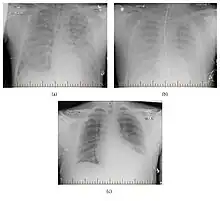

| Hantavirus pulmonary syndrome on chest X-ray | |